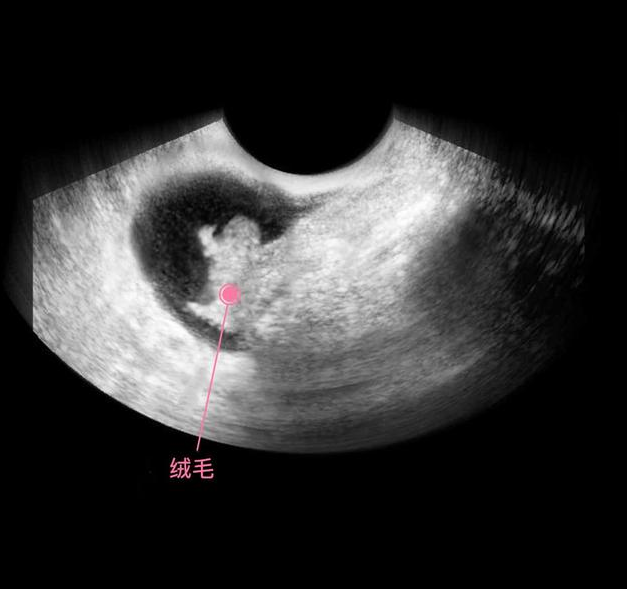

上图是怀孕后,丛查受精卵经过了分裂,形成了细胞团,这个阶段还不能叫胎儿,只能叫胚泡,胚胎开始发育并分泌人体促绒毛性腺激素,不过此时的含量还很少,用验孕棒根本测试不出来。

细胞继续分化,有的分化成胎儿的大脑,有的分化成胎儿的肾脏和肝脏,还有的分化成心脏等,这个时期的宝宝叫做胎芽,依靠着卵黄囊提供的营养,还用不到母体的营养呢,所以此时有了怀孕反应,没有食欲也没有关系,对胎儿发育的影响不大。